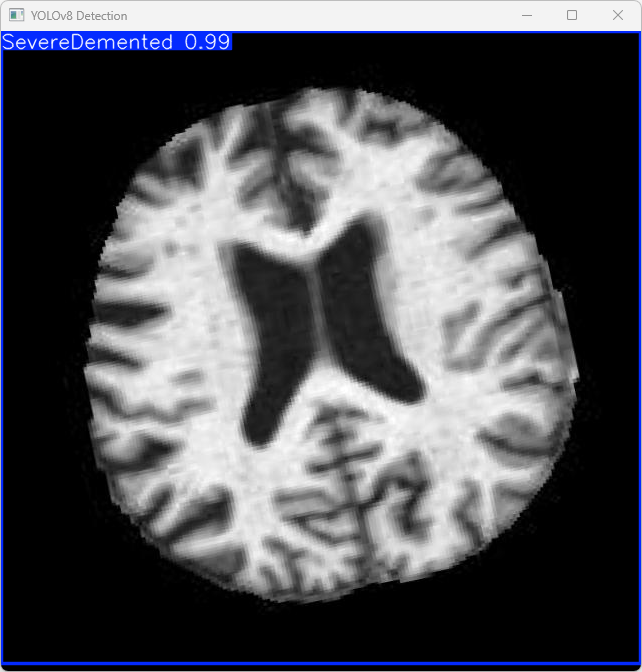

执行imgTest.py代码后,会将执行的结果直接标注在图片上,结果如下:

这段输出是基于YOLOv8模型对图片“imagetest.jpg”进行检测的结果,具体内容如下:

图像信息:

(1)处理的图像路径为:TestFiles/imagetest.jpg。

(2)图像尺寸为 640×640 像素。

检测结果:

(1)模型在该图片上检测到 1 个严重痴呆(”1 SevereDemented”)

处理速度:

(1)预处理时间: 14.4 毫秒

(2)推理时间: 5.0 毫秒

(3)后处理时间: 168.1 毫秒

模型在处理图片时非常高效,成功检测出 1 个看屏幕实例,并将结果保存到了指定目录。